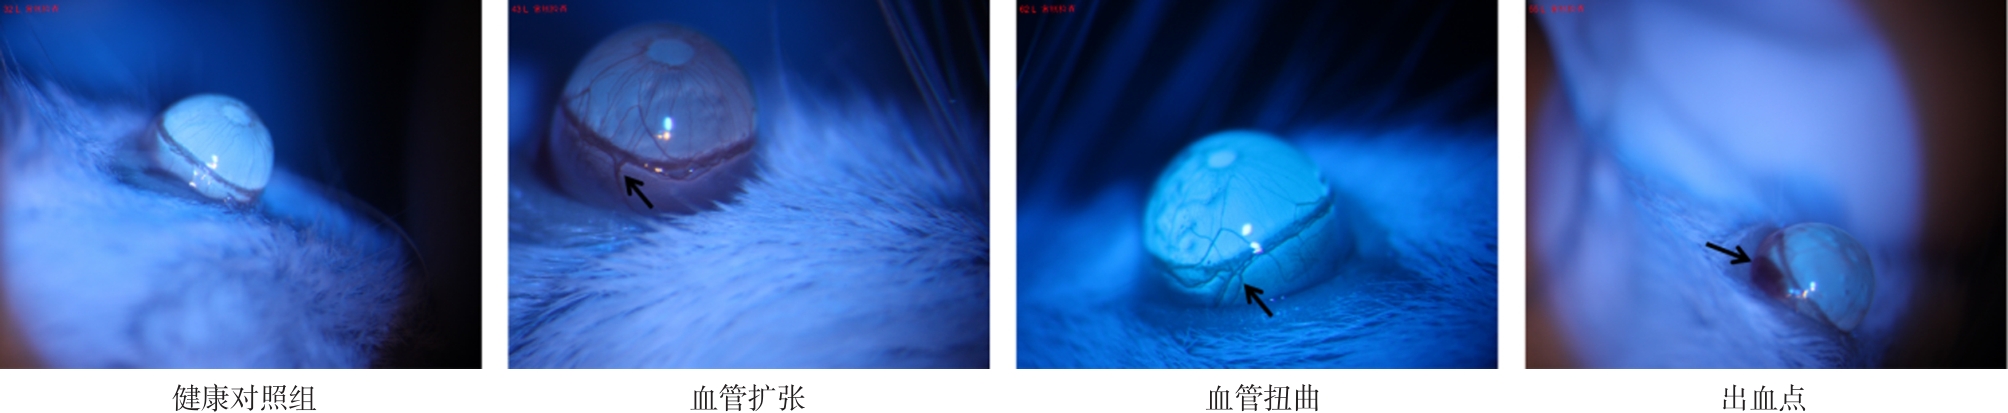

Objective This study aims to investigate the pathological role and molecular mechanisms of pericyte depletion in neuropsychiatric lupus (NPSLE) and to assess the potential of the PDGFR-β signaling pathway as a novel therapeutic target for NPSLE. Methods NPSLE models were established using 8-week-old female MRL/lpr mice, from which those exhibiting abnormal behaviors were selected for further analysis. The PDGFR-β signaling pathway was modulated using an agonist to promote pericyte proliferation or an inhibitor to suppress pericyte apoptosis. The effects of these treatments on blood-brain barrier (BBB) integrity, eye-signs in blood stasis syndrome, neuronal integrity, and tight junction protein expression were evaluated. Evans blue staining, H&E staining, Nissl staining, and immunofluorescence staining were employed to assess the expression of tight junction proteins (Cadherin, ZO-1), endothelial cell markers (CD31), and pericyte markers (NG2). Results Mice in the NPSLE group exhibited significant anxiety, depression, and cognitive impairment. In the PDGFR-β inhibition group, eye-signs in blood stasis syndrome scores were significantly elevated (P < 0.01), BBB permeability was markedly increased (P < 0.001), neuronal numbers were significantly reduced, tight junction protein expression was diminished, and pericyte depletion was aggravated. Conversely, the PDGFR-β agonist group showed a significant reduction in eye-signs in blood stasis syndrome scores (P < 0.01), improved pericyte survival, enhanced expression of tight junction proteins, reduced neuronal damage, and restoration of BBB function (P < 0.001). Immunofluorescence staining further confirmed that PDGFR-β activation significantly protected pericytes. Conclusions Pericyte depletion is closely associated with increased BBB permeability and exacerbation of eye-signs in blood stasis syndrome. Modulation of the PDGFR-β signaling pathway may provide a promising therapeutic strategy for NPSLE.